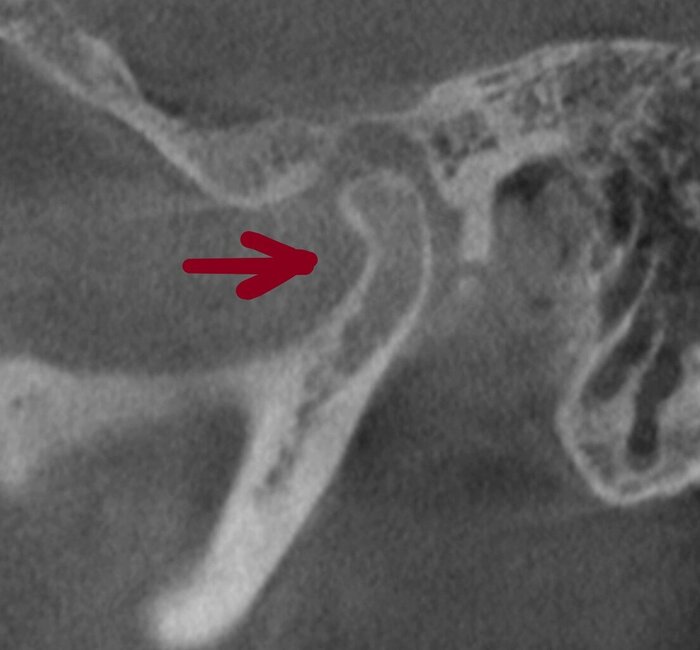

А теперь посмотрим на картину с антагонистами.

Важно - мы не переделывали прикус! А повторили тот, что у пациента уже был, только высоту вернули.

Проверяем попадание в прикус.